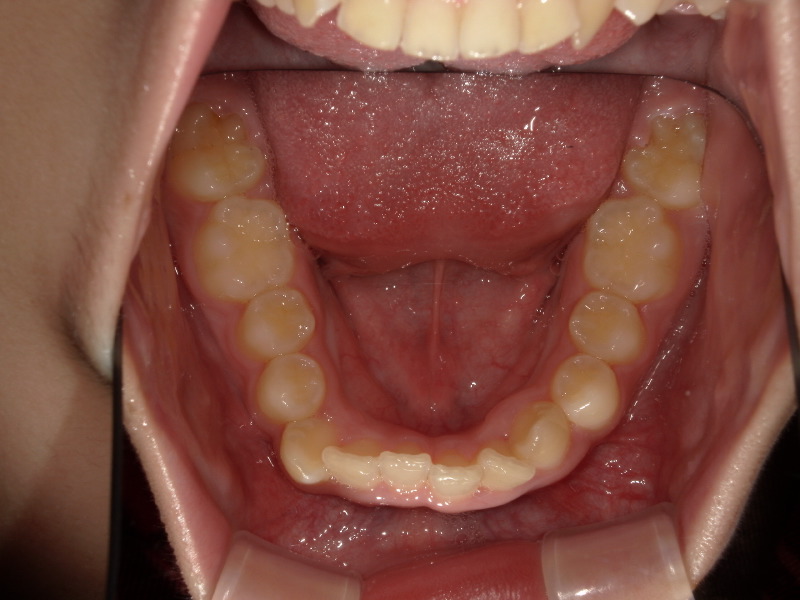

下の歯並び

噛み合わせが深かったのが前にくる=下顎は前に成長しています。

そのため、顎の位置変化が起き、下の顎のアーチは大きくなり、がたつきも改善していきます。

こちらも一年半の経過です。

既に永久歯列なことと、一番奥の親知らずの手前まで歯が出てきていますが、綺麗に入ってきています。